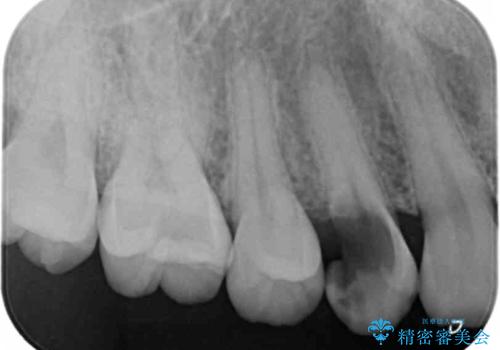

- メンテナンスでいらっしゃった患者様です。

歯を保護するためのナイトガードを装着していきます。

厚みのあるナイトガードを調整することで、夜間の歯ぎしりにより歯にかかる強い力を分散させることができます。